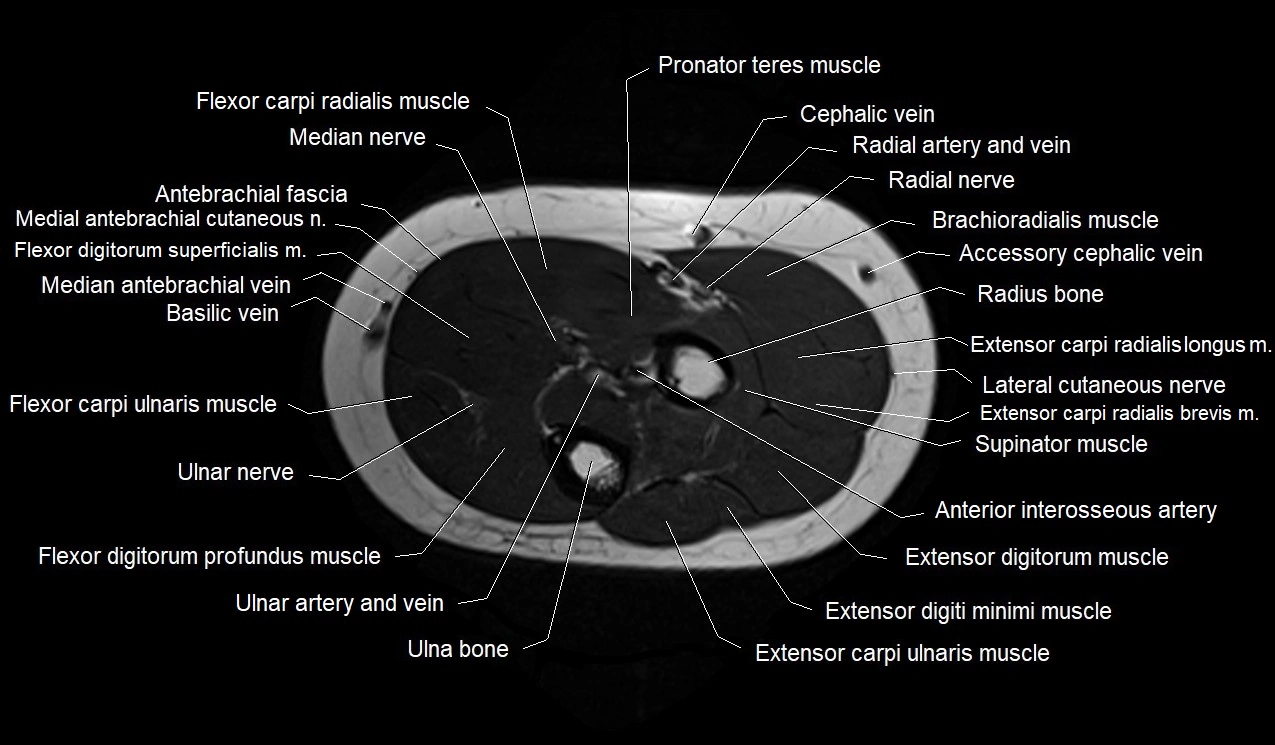

MRI images

image